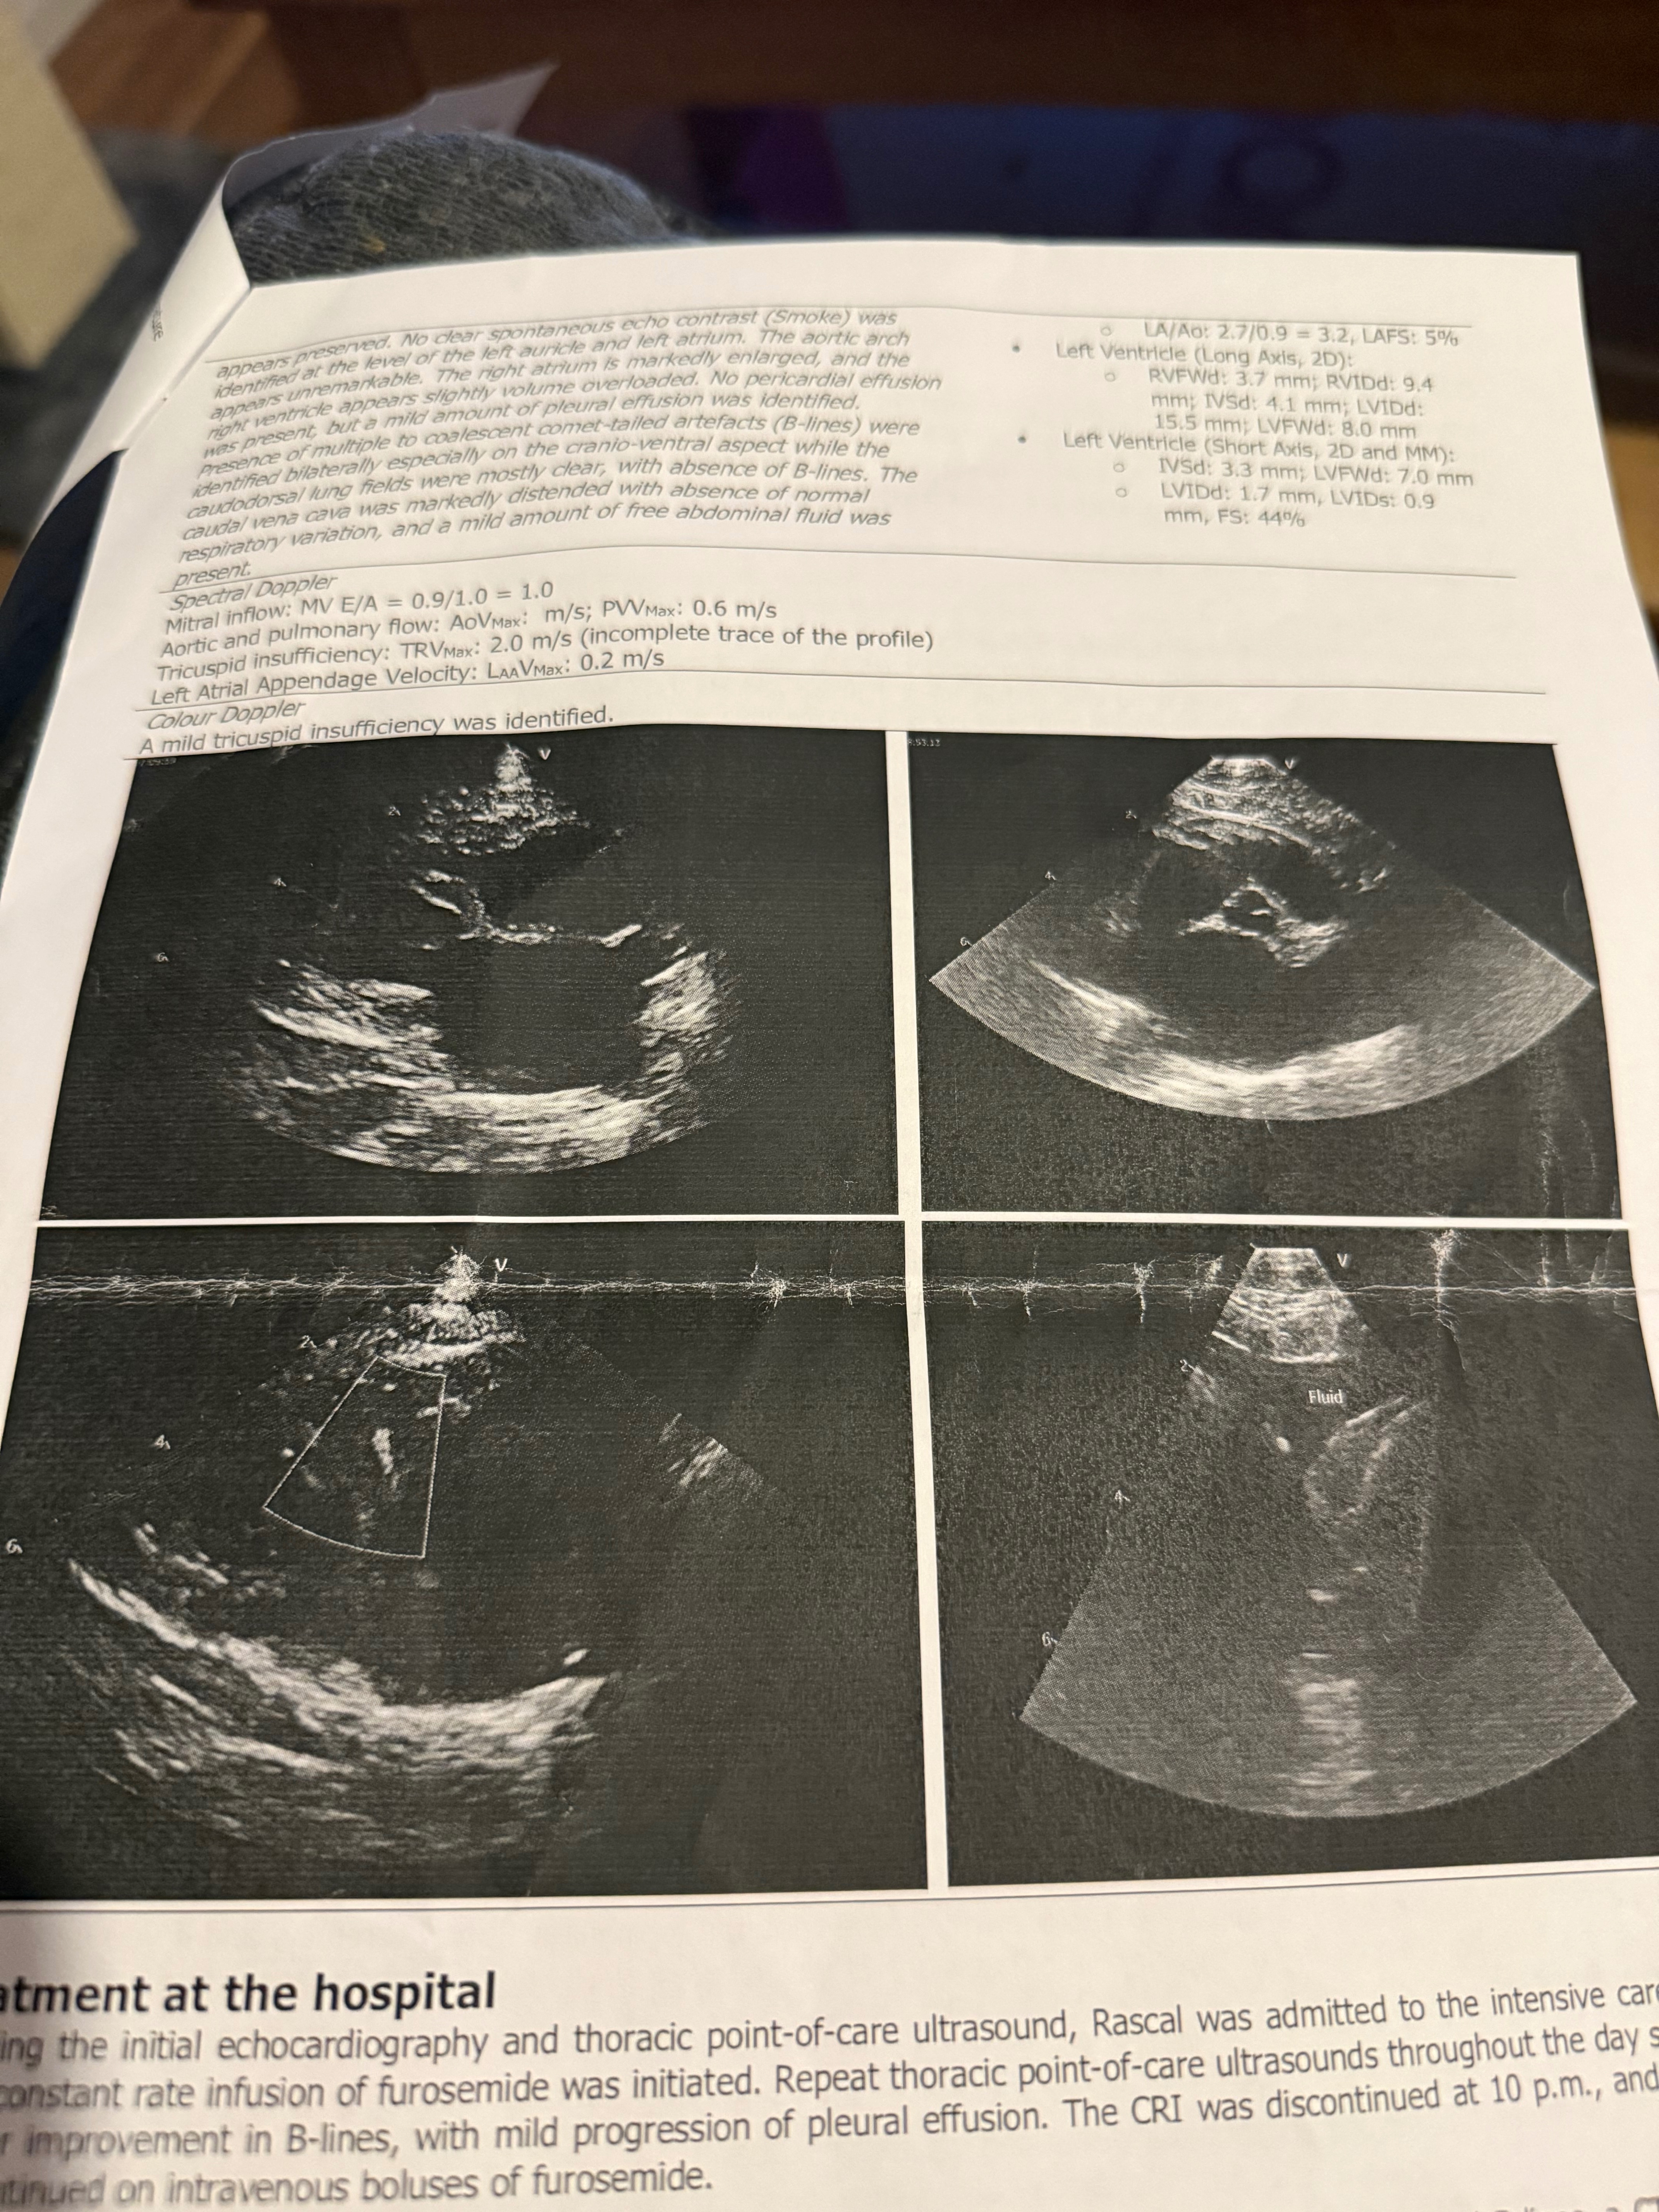

Hi my name is Kelly, Rascal is an 11 year old boy who has asthma and arthritis and has been battling for 6 years with the condition and was doing well, on Monday morning I let him out and suddenly he collapsed and could not breathe well, we took him to our vets where after extensive testing they told us he had fluid in his body so we were referred to Glasgow small animal hospital where he underwent an cardio echo, a ct scan, multiple blood tests, and was diagnosed with severe feline hypertrophic cardiomyopathy, we stay in Perth and had to travel back there and forth via taxi which was not cheap, he is now on monthly medication and has a very high total outstanding in his vet bills, rascal has helped me so much and now it’s time to help him, please if you can help us to be able to get him the treatment and help us with his huge vet bills too.